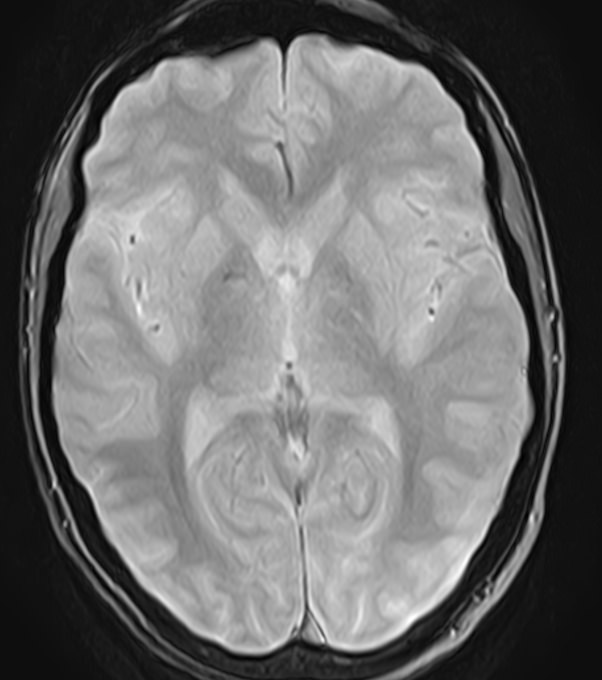

Для диагностики поражения черепно-мозговых нервов, а также оценки состояния окружающих их тканей и визуализации сосудистой сети головного мозга в клинике «Доступная медицина» проводится комплексное обследование МРТ головного мозга + Мр-ангиография головного мозга + МР-венография головного мозга + черепно-мозговые нервы. Данное обследование включает в себя несколько протоколов: стандартный – для оценки состояния всех структур головного мозга и дополнительные – для изучения очагов поражения черепных нервов и визуализации всей сосудистой системы головного мозга.

Исследования выполняются на современном высокопольном томографе экспертного класса TOSHIBA VANTAGE TITAN 1,5 Тесла, который использует разные режимы сканирования с толщиной среза от 1мм в различных плоскостях с последующей цифровой обработкой полученных данных для создания трехмерных изображений. МР-ангиография отображает состояние артериальной системы кровоснабжения головного мозга. МР-венография головного мозга позволяет детально изучить особенности венозного русла головного мозга.

Компьютерная программа обрабатывает данные, полученные при сканировании, и формирует объемные изображения как самого мозга, так и сосудистой системы в отдельности без прилегающих тканей. Методики применяются одновременно и взаимодополняют друг друга.